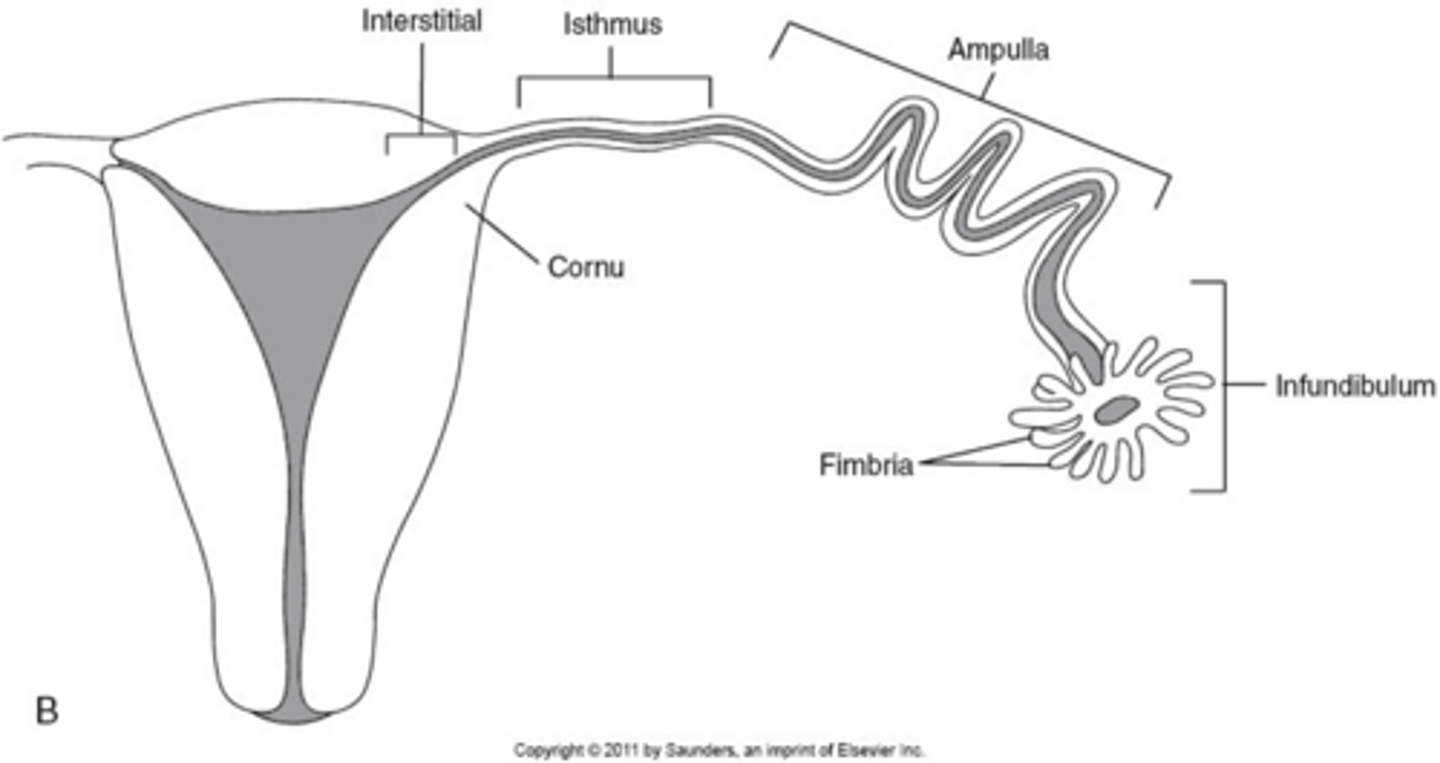

What are the 4 segments of the fallopian tubes?

1. interstitial

2. isthmus

3. ampulla

4. infundibulum

What part of the fallopian tube is the widest segment where fertilization occurs?

ampulla

What part of the fallopian tube is the most dangerous to have an ectopic pregnancy?

interstitial bc most vascular